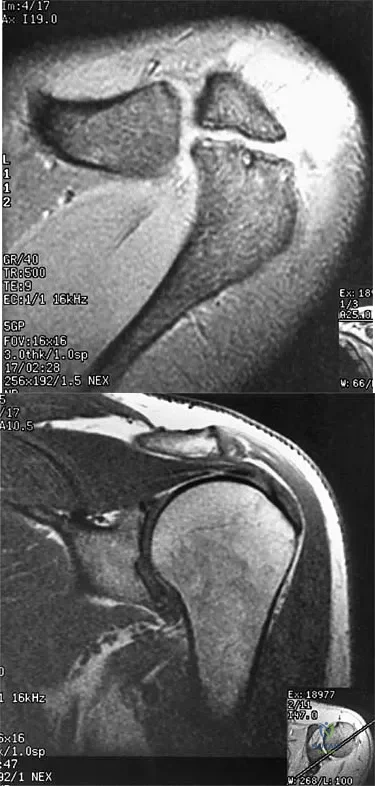

Question 17

A 47-year-old male tennis player has pain in his nondominant shoulder that has failed to respond to 4 months of nonsurgical management. Examination reveals acromial tenderness and pain at the supraspinatus tendon insertion. He has a positive impingement sign, pain on forward elevation, and minimal cuff weakness. The MRI scans are shown in Figures 30a and 30b. To completely resolve his symptoms, treatment should consist of

Explanation